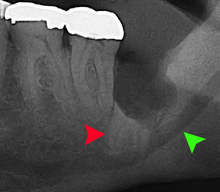

For partially impacted teeth in those over 20 year of age, the most common pathology seen, and the most common reason for wisdom teeth removal, is pericoronitis or infection of the gum tissue over the impacted tooth. The bacteria associated with infections include Peptostreptococcus, Fusobacterium, and Bacteroides bacteria. The next most common pathology seen is cavities or tooth decay. Fifteen percent of people with retained wisdom teeth exposed to the mouth have cavities on the wisdom tooth or adjacent second molar due to a wisdom tooth. The rate of cavities on the back of the second molar has been reported anywhere from 1% to 19% with the wide variation attributed to increased age.[10]

In five percent of cases, advanced periodontitis or gum inflammation between the second and third molars precipitates the removal of wisdom teeth.[3]:141[4] Among patients with retained, asymptomatic wisdom teeth, roughly 25% have gum infections (periodontal disease).[11]:ch13 Teeth with periodontal pockets of greater than 5mm have tooth loss rates that start at 10 teeth lost per 1000 teeth per year at 5mm to a rate of 70 teeth lost per year per 1000 teeth at 11mm.[12]:57 The risk of periodontal disease and caries on third molars increases with age with a small minority (less than 2%) of adults age 65 years or older maintaining the teeth without caries or periodontal disease and 13% maintaining unimpacted wisdom teeth without caries or periodontal disease.[13] Periodontal probing depths increase over time to greater than 4 mm in a significant proportion of young adults with retained impacted wisdom teeth which is associated with increases in serum inflammatory markers such as interleukin-6, soluble intracellular adhesion molecule-1 and C-reactive protein.[14]